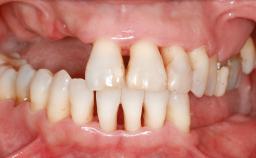

A 20-year-old woman was referred for implant therapy in 2004. Her medical history revealed no significant findings, and neither did she smoke nor take any medications. An extraoral examination revealed no abnormalities of the skin, hair or nails. The intraoral examination revealed only 11 permanent teeth clinically. These were normal in shape, size, and color. In addition, eight retained deciduous teeth (53, 62, 63, 71, 72, 73, 81, 82) were present. No abnormalities were detected during the general examination. The family history revealed that the patient’s father and two sisters were on record with similar conditions. The clinical examination revealed a thick gingival biotype. No recession of the attached gingiva was noted, but the retained deciduous teeth were mobile and unsightly. As a syndrome had not been diagnosed, the case was categorized as non-syndromic oligodontia.

Periodontal Phenotype Low-scalloped, thick Medium-scalloped, medium-thick High-scalloped, thin

Shape of Tooth Crowns Rectangular Triangular